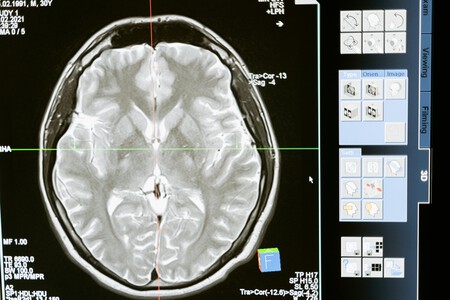

Nunca es demasiado pronto para ser consciente de las señales de advertencia de este trastorno cerebral común, de hecho, la ciencia estudia sus síntomas para poder detectar de forma temprana su aparición y así poder frenar el deterioro lo antes posible. “La enfermedad de Alzhéimer en realidad comienza en el cerebro décadas antes de que tengas algún síntoma”, compartió recientemente en TikTok el Dr. Daniel Amen, psiquiatra doblemente certificado y experto en imágenes cerebrales en California.